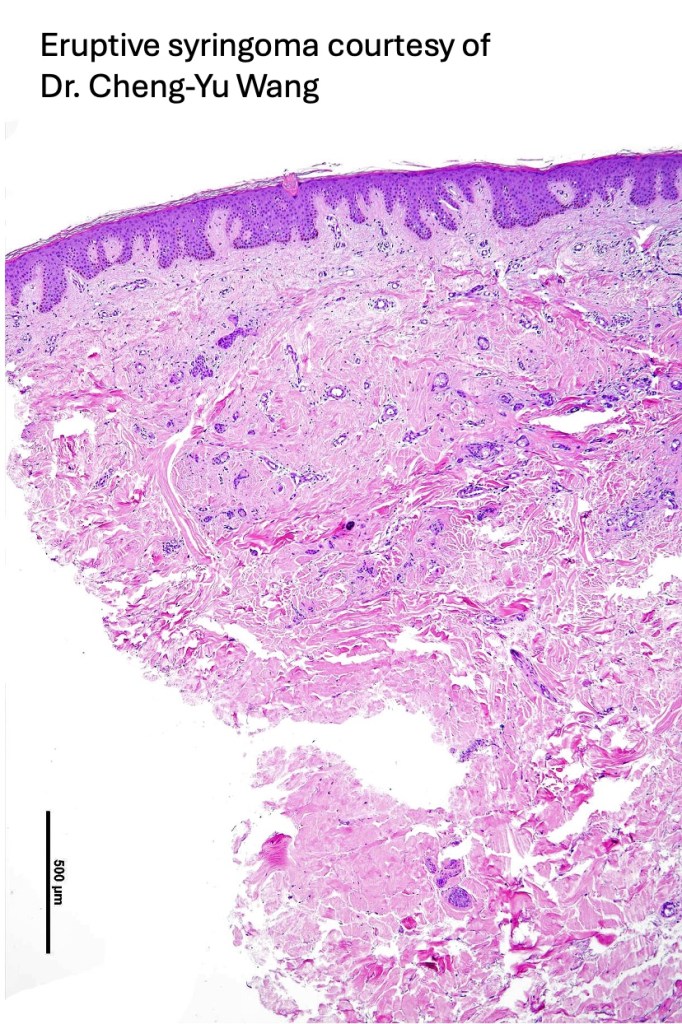

Histological features

•Dermal lesion composed of epithelial stands & ducts dispersed in a fibrous stroma